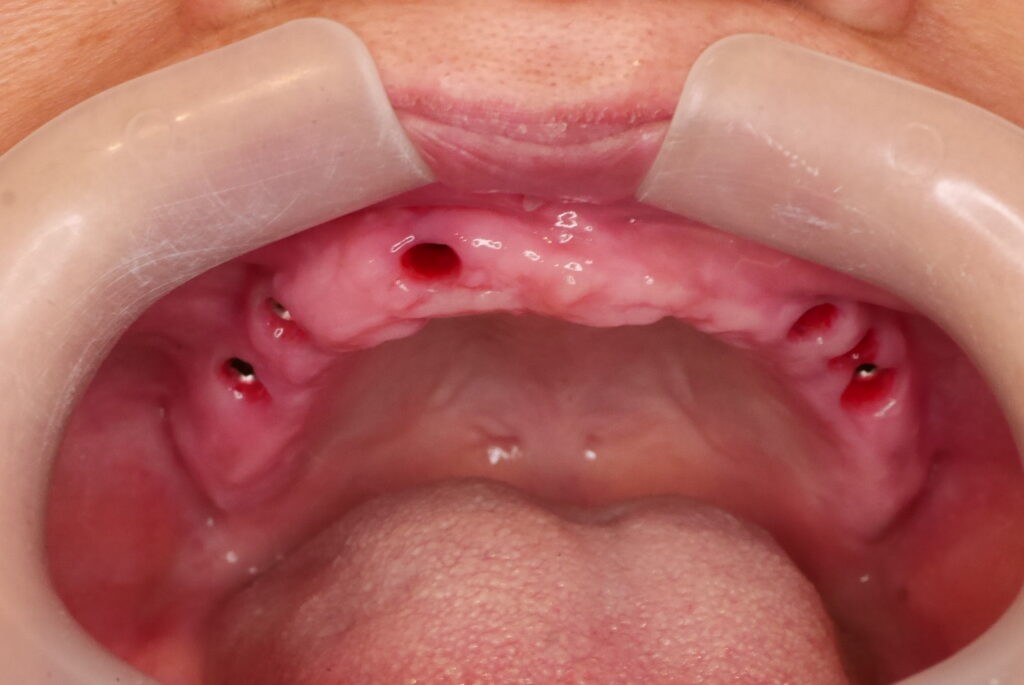

上顎長期缺牙,只剩幾個殘存牙根

殘根拔除後,植入6支人工牙根